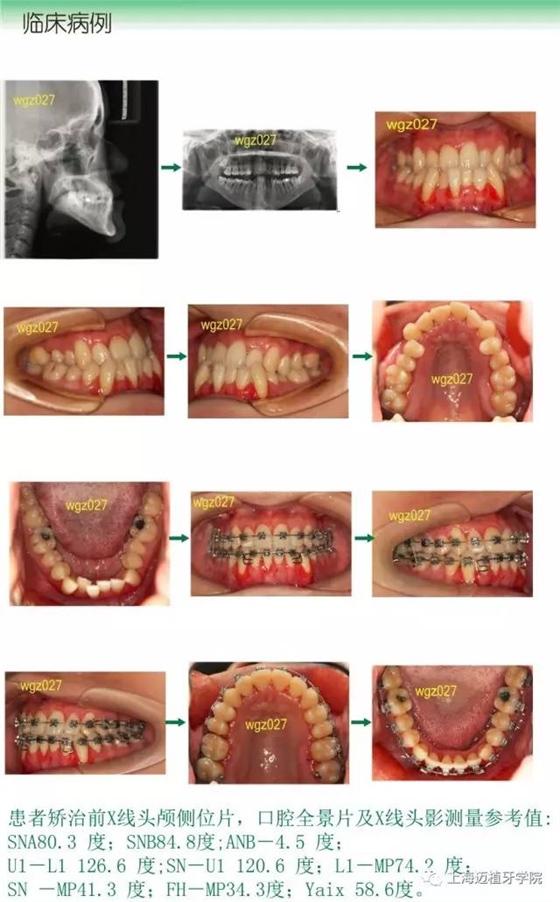

C、X線頭影測(cè)量分析